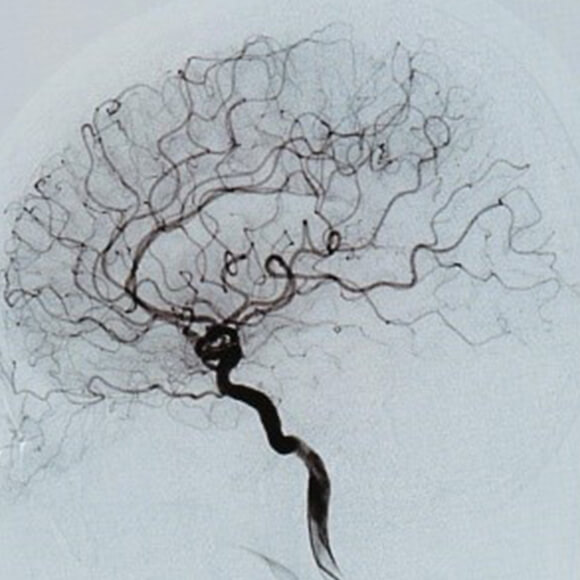

アンギオ検査部⾨

アンギオ検査とは⾜の付け根・⼿⾸・肘などからカテーテルと呼ばれる細い管を⾎管内に挿⼊し、造影剤を注⼊しながら⾎管のX線撮影を⾏う検査です。これにより⾎管の閉塞・狭窄やがんなどの臓器疾患の診断が可能となります。

近年、アンギオ検査は⾎管造影撮影による画像診断だけでなく、引き続き治療を⾏うIVR(InterVentional Radiology)が盛んに⾏われています。

治療部位に応じて⼿技はさまざまであり、⼼臓や四肢の狭くなったり詰まったりした⾎管にはバルーンと呼ばれる⾵船のついた管やステントと呼ばれる⾦属製の筒を挿⼊、または⾎管を拡張させるような薬を流すことで正常な状態に戻したり、症状を抑えるような治療を⾏います。がん疾患については、腫瘍を栄養している⾎管までカテーテルを進め、抗がん剤や塞栓物質を⽤い腫瘍を弱らせ、縮⼩させる動脈化学塞栓術を⾏います。その他、動脈瘤や外傷等による出⾎部位の⽌⾎については、コイルと呼ばれる塞栓物質により⾎管を詰まらせる⾎管塞栓術を⾏います。

当センターでは、⾎管内治療だけでなくX線透視下で⾏う検査及び治療についてはアンギオ装置を有効に活⽤できる体制を整備しております。

頭部⾎管

頭部⾎管